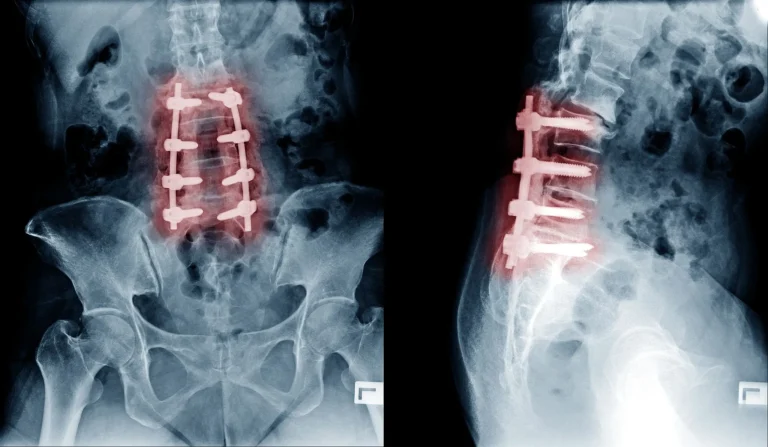

X-ray showing spinal fusion with metal screws and rods in the lumbar region.

Leads to Unnecessary Fusion